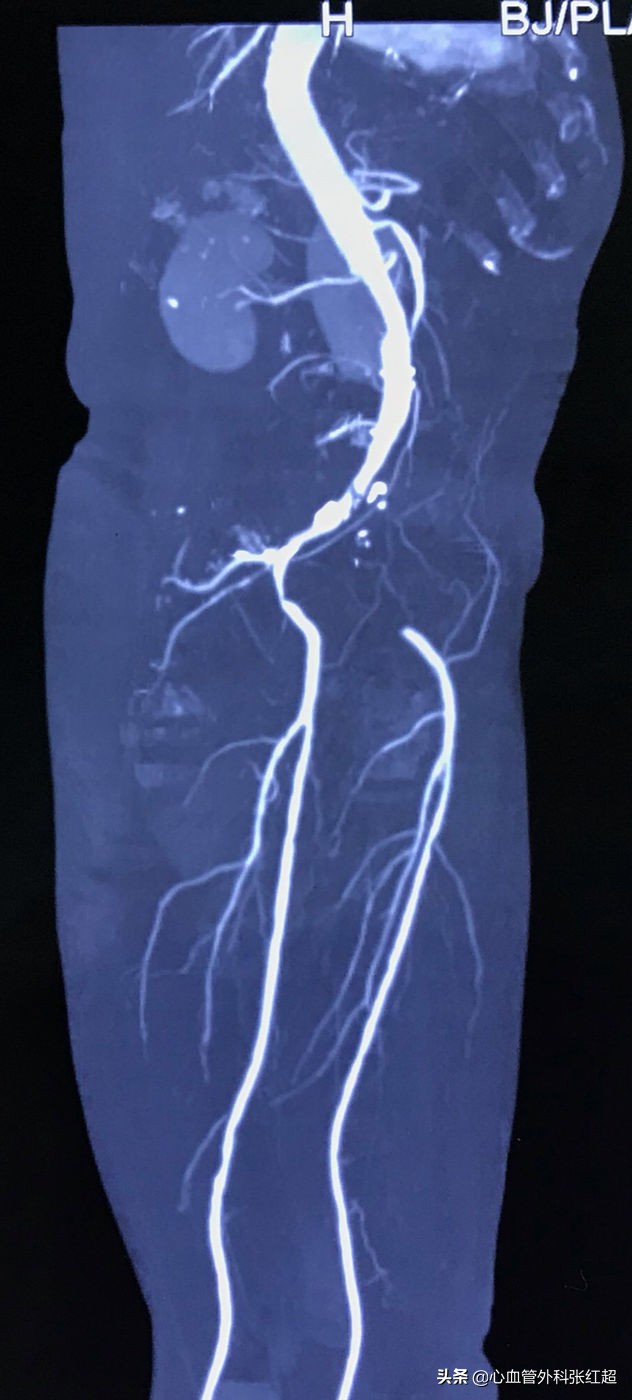

●LCIA闭塞全程闭塞病变